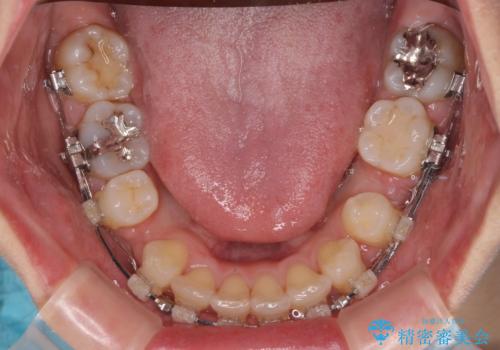

- 前歯のクロスバイトと口元の膨らんだ横顔の印象を気にして来院された患者様です。

しかしながら。そのまま叢生を解消すると横顔が突出した印象になる可能性が高かったため、上下左右の小臼歯4本を抜歯して、ワイヤー装置にて矯正治療を行うこととしました。

上下左右の第一小臼歯4本を抜歯して治療を行うことがセオリーでしたが、左下は第二小臼歯が銀歯であったため、イレギュラーではありますが、そちらを抜歯しました。

その影響で治療期間は長くなりましたが、処置していない歯を保存することができました。